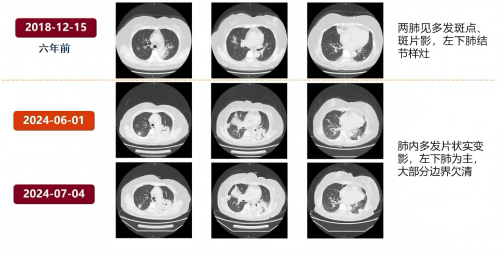

回顾病史,患者6年前曾行肺部CT检查,提示两肺多发斑片斑点影,左肺下叶有结节样灶,经门诊左氧氟沙星抗感染治疗后,6年内未再进行肺部CT复查。

患者2月余前出现发热,体温最高达39.8℃,1天后出现咳嗽咳黄痰。门诊查血常规、C 反应蛋白未见明显异常,胸部CT平扫提示两肺多发炎症及实变灶。给予头孢曲松联合左氧氟沙星抗感染治疗14天,复查胸部CT显示病灶较前无明显吸收。

出院1个月后,患者进行门诊随访,胸部CT显示左肺渗出略有吸收,但大片实变影吸收不显著,左侧胸腔积液减少,肺内仍存在多发斑片。8月16日,患者再次入院。鉴于上次住院时肿瘤指标升高,尤其是CA199,需进一步排查胃肠道情况。